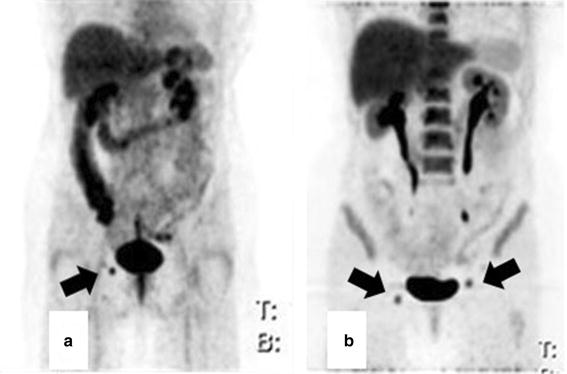

Patient no. 15 (female, 64 years old), rectal adenocarcinoma, T3 N0 Mx, posttherapeutic PET/CT studies a F-18 FDG maximum intensity projection (MIP): F-18 FDG avid inguinal lymph node on the right side b F-18 FLT MIP: F-18 FLT avid bilateral inguinal lymph nodes

The SUVmax of lymph node metastases in F-18 FDG studies was 9.1 ± 7.6 (median 8.0, range 1.5–18.2) before RCT and 4.5 ± 1.3 (median 4.3, range 3.1–6.3) after RCT, respectively. In F-18 FLT imaging, the mean SUVmax was 4.9 ± 1.6 (median 4.9, range 2.6–6.6) before RCT and 5.9 ± 2.1 (median 6.3, range 3.1–7.9) after RCT, respectively.

After RCT, inguinal lymph nodes were seen in a few patients as reported before [31], These findings could be found either unilaterally or bilaterally. Most interestingly, the same inguinal lymph nodes could be seen in F-18 FDG and F-18 FLT PET/CT in 3 patients.

In the study of Perez et al. [31], the relevance of F-18 FDG positive inguinal lymph nodes in patients with rectal cancer after neoadjuvant chemoradiation was evaluated. They postulated that patients with persisting F-18 FDG uptake in inguinal lymph nodes had a worse prognosis. We could not support this hypothesis, since survival of our patients was favorable. Furthermore lymphatic drainage of rectal cancer cells into inguinal lymph nodes is a matter of controversy and rarely seen [32].

Two F-18 FLT PET/CT studies exhibited inguinal nodal uptake challenging the selectivity of F-18 FLT as a proliferation marker. Troost et al. [33] analyzed the value of F-18 FLT PET for determining the lymph node status in 10 patients with squamous cell carcinoma of the head and neck. Nine patients showed F-18 FLT PET-positive lymph nodes, but only 3 of these patients had histologically proven metastases. In the remaining 7 patients, an abundance of Ki-67 and iododeoxyuridine staining of B-lymphocytes in germinal centers of PET-positive lymph nodes could be seen, explaining the high rate of false-positive findings.